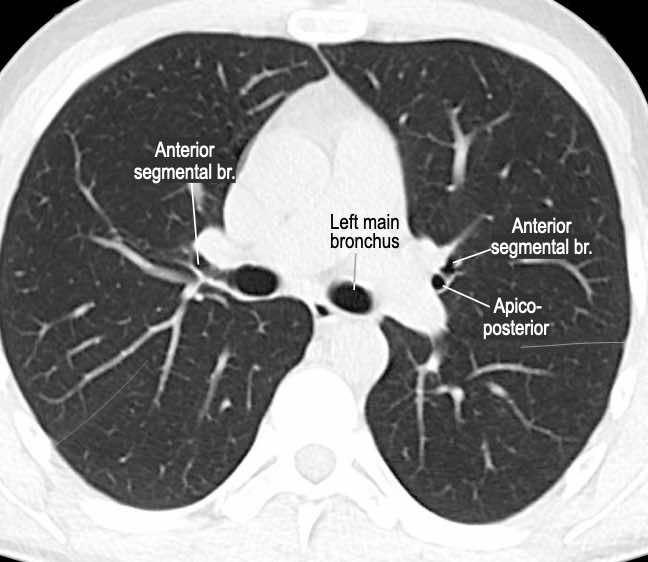

Phế quản trên CT

Cuộn qua các hình ảnh để quan sát khí quản phân chia thành phế quản chính phải và trái, sau đó tiếp tục phân chia thành các phế quản thùy và phế quản phân thùy.